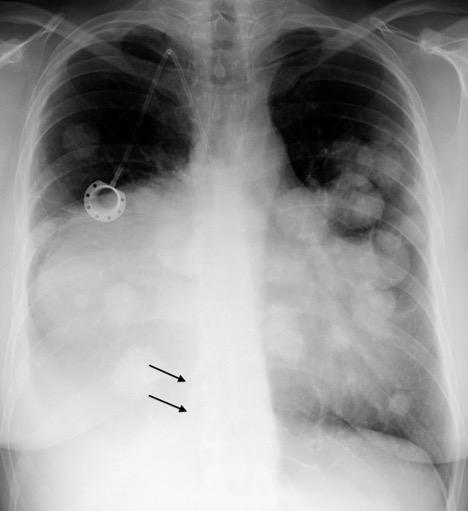

Hepatomegalia metastática. Ca. de pulmón